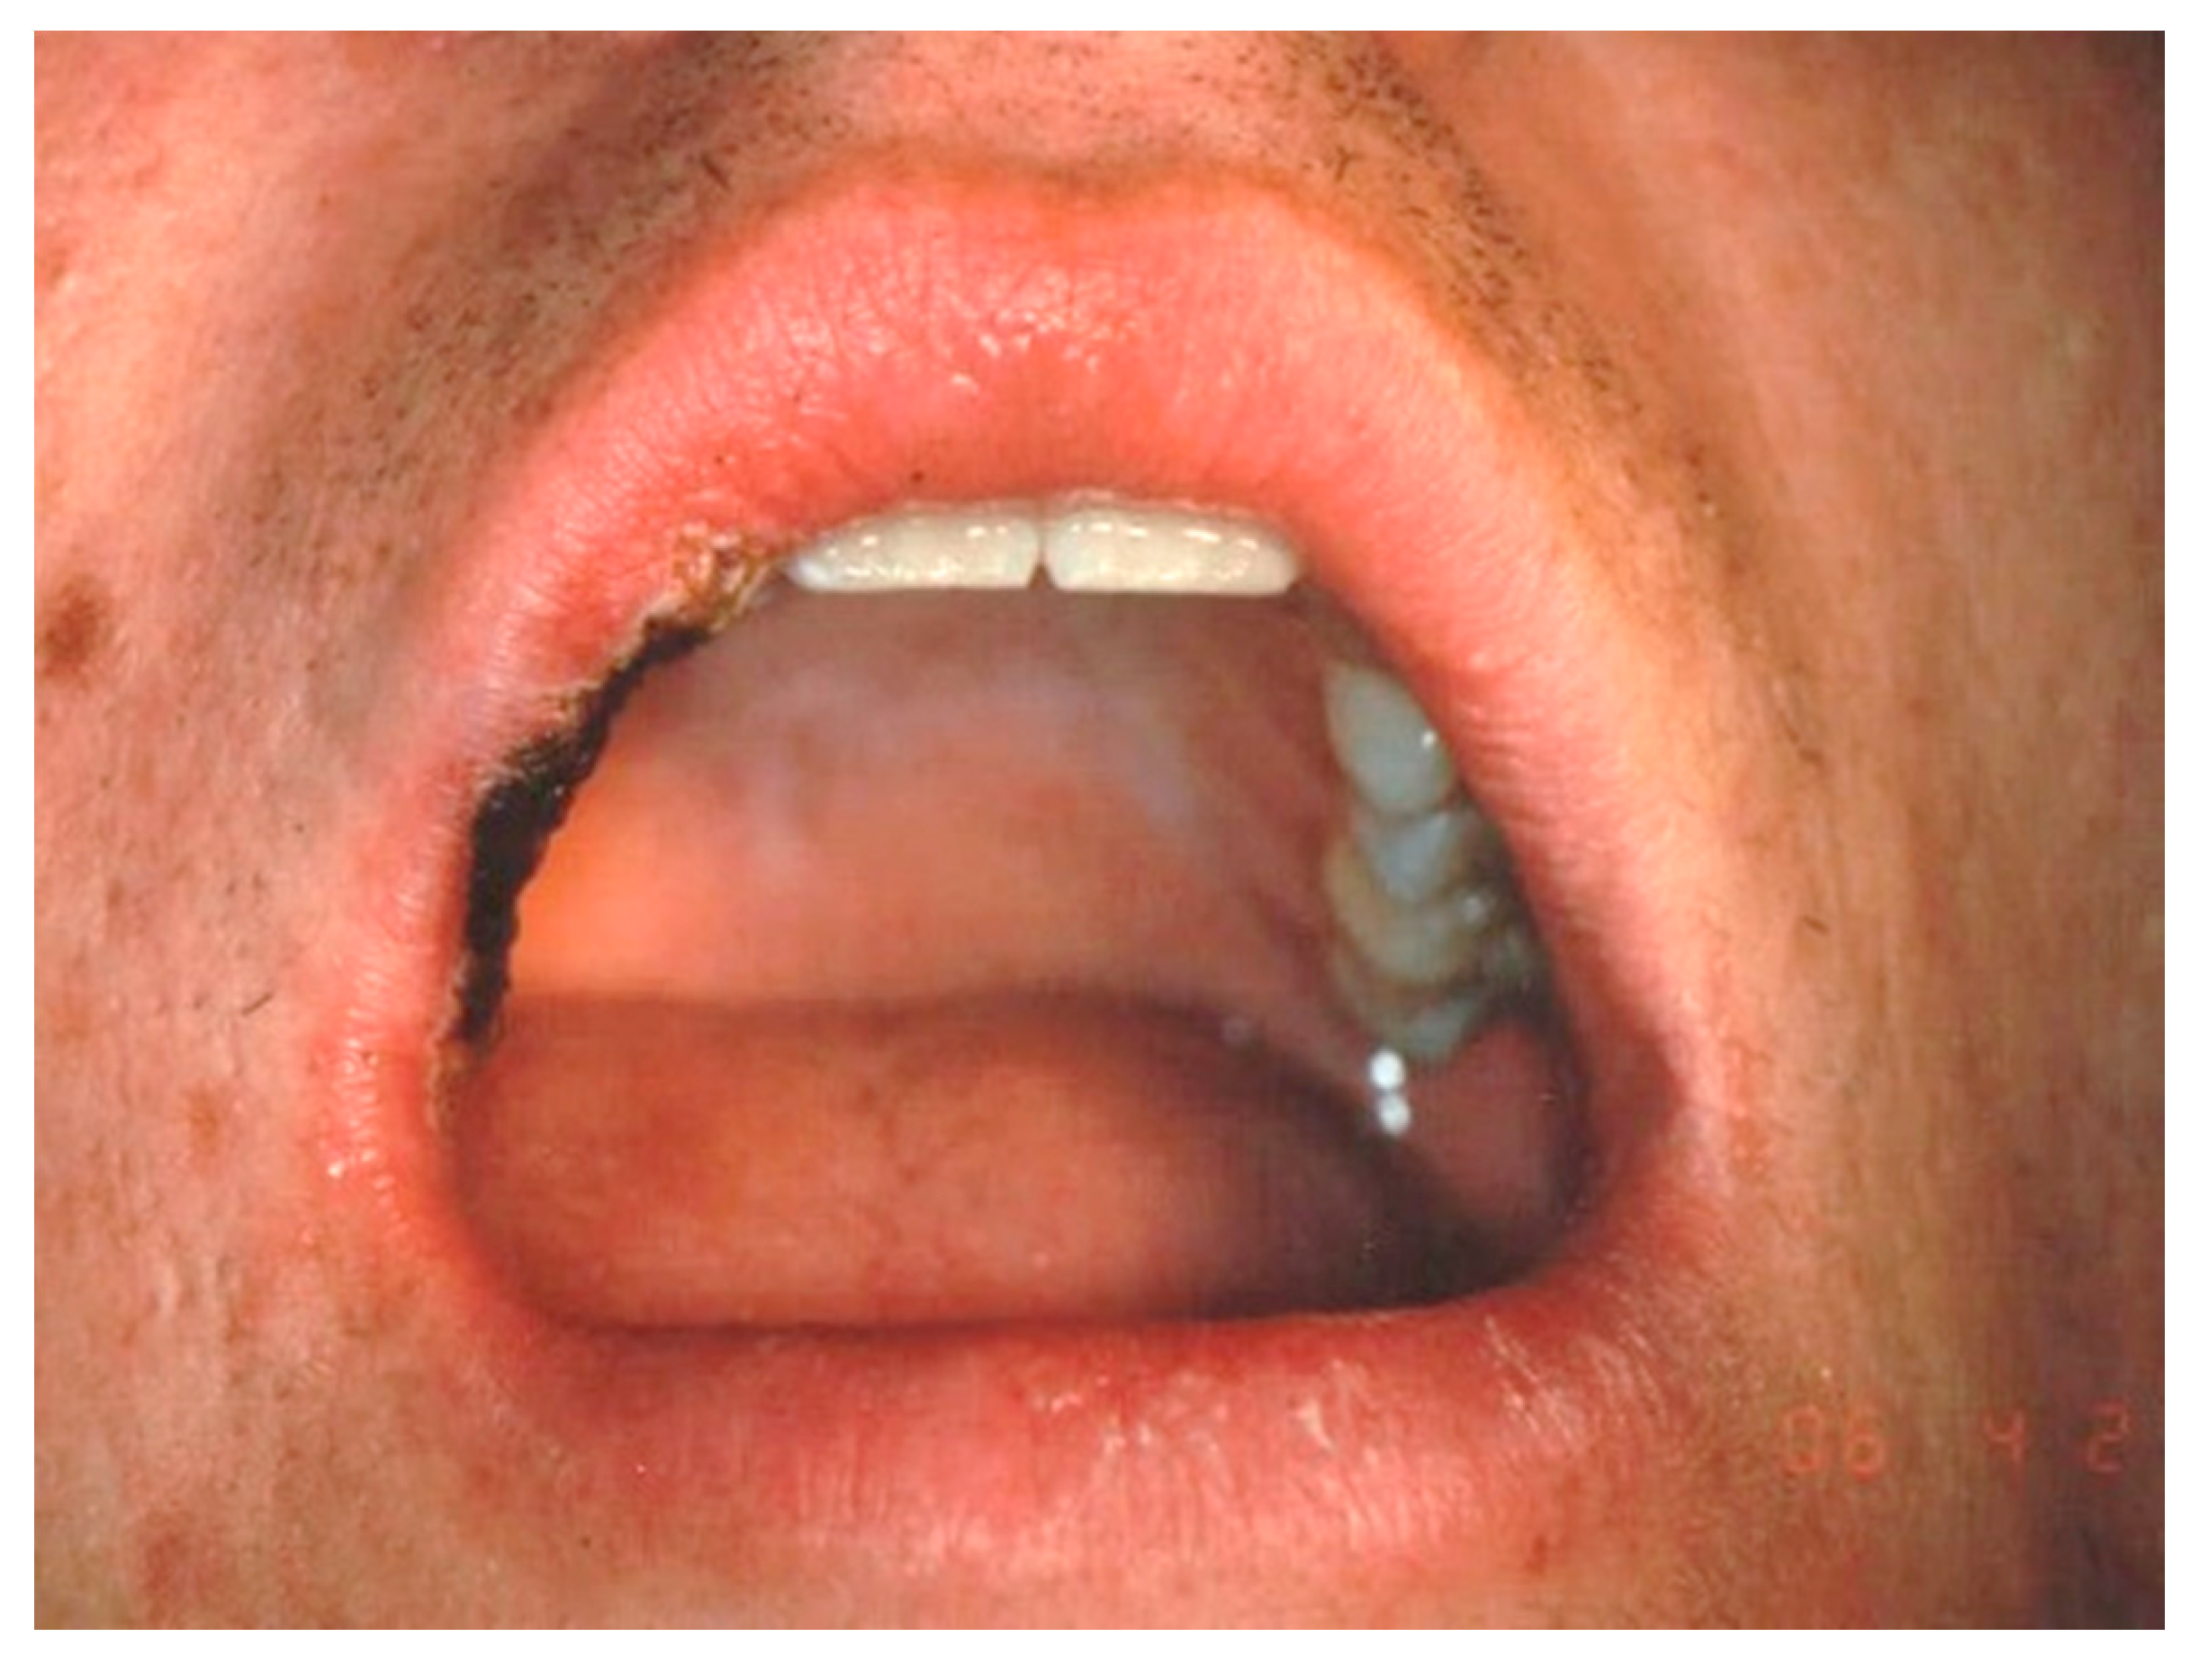

Aesthetic Treatment Outcomes of Capillary Hemangioma, Venous Lake, and Venous Malformation of the Lip Using Different Surgical Procedures and Laser Wavelengths (Nd:YAG, Er,Cr:YSGG, CO2, and Diode 980 nm)

1. Introduction